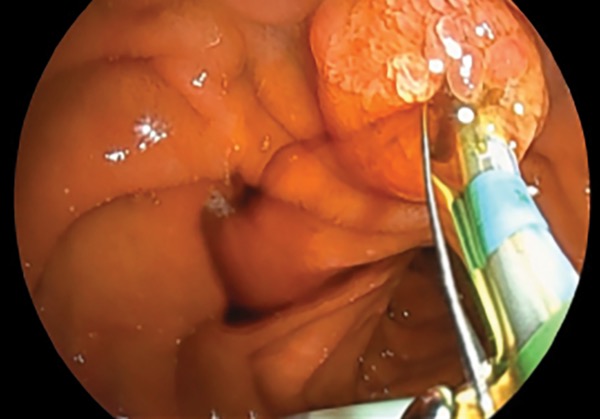

A 64-year-old man presented with jaundice, biliary dilation, and a new mass lesion in the head of the pancreas. EUS was performed with the EG-740UT scope for staging and sampling of the primary mass lesion, which confirmed pancreatic adenocarcinoma. Using the same scope, the endoscopist was able to perform transpapillary endoscopic retrograde cholangiopancreatography (ERCP) due to the strength and deflection of the elevator and view of the accessory channel allowed by this new scope design (Figure 3). A fully covered metal stent was deployed across the distal malignant biliary obstruction for palliation of the stricture after biliary sphincterotomy (Figure 4).